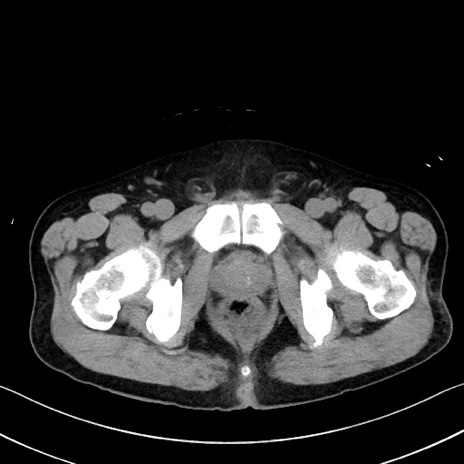

症例35(横断像)

【症例】70歳代 男性

【主訴】腹部膨満、嘔吐

【現病歴】昨日より腹部膨満感出現。本日増悪し、仙痛出現。嘔吐あり、受診。

【既往歴】糖尿病、胆摘後

【身体所見】BP 149/80mmHg、HR 74/min、BT 35.9℃、腹部:膨満、軟、圧痛なし。腸雑音減弱あり。上腹部正中切開瘢痕あり。

【データ】WBC 13500、CRP 1.72